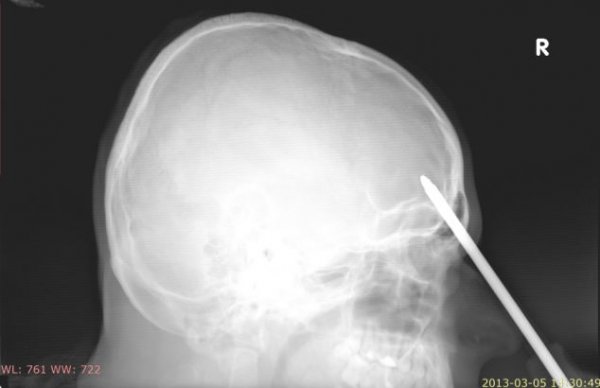

یک مرد لهستانی که در حادثهای یک پیچگوشتی در پیشانیاش فرو رفته بود با تلاش سه ساعته پزشکان از نابینایی نجات یافت. این مرد 25ساله که به خواسته خودش هویتش فاش نشده هنگام انجام کارهای باغبانی در باغچه جلوی خانهاش ناگهان پایش سرخورد و یک پیچگوشتی 5سانتیمتری در پیشانیاش فرو رفت.

به گفته پزشکان در کمال خوششانسی این پیچگوشتی از کنار مغز عبور کرده و در جایی قرار گرفته بود که با مرکز بینایی این مرد تنها چند میلیمتر فاصله داشت. این مرد که به رغم شدت جراحت و خونریزی با تلاش فراوان پیچگوشتی را در جای خود ثابت نگه داشته بود، با پای خودش به در خانه همسایه رفت و از آنها خواست تا اورژانس را خبر کنند.

پزشکان پس از عکسبرداریهای متعدد از سر این مرد او را بلافاصله به اتاق عمل بردند و طی سه ساعت عمل پیچگوشتی را از پیشانیاش بیرون کشیدند.